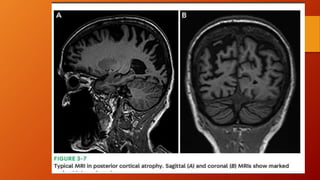

• La Neuroimagen muestra una atrofia progresiva bilateral , precoz

de la región temporal medial , hipocampo y corteza entorrinal.

• Despues hay atrofia parieto-temporal .